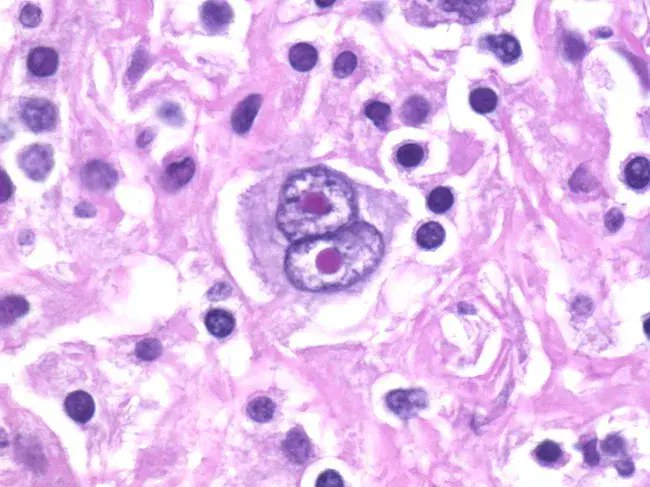

1/ It has long been known that microenvironmental signals can drive tumor growth, particularly in tumors that are rich in non-malignant cells — yet the specific signals have remained a mystery. Hodgkin lymphoma is the exemplar, with rare tumor cells (<1%!) reliant on such signals. We set out to define these signals 🧵 Paper: rdcu.be/e2KuZ

@Vignesh_Shan seeks to identify pro-tumorigenic growth factors in the environment around follicular lymphoma cells and elucidate how these growth factors promote cancer survival and proliferation, with the goal of developing of new treatments that block these interactions.